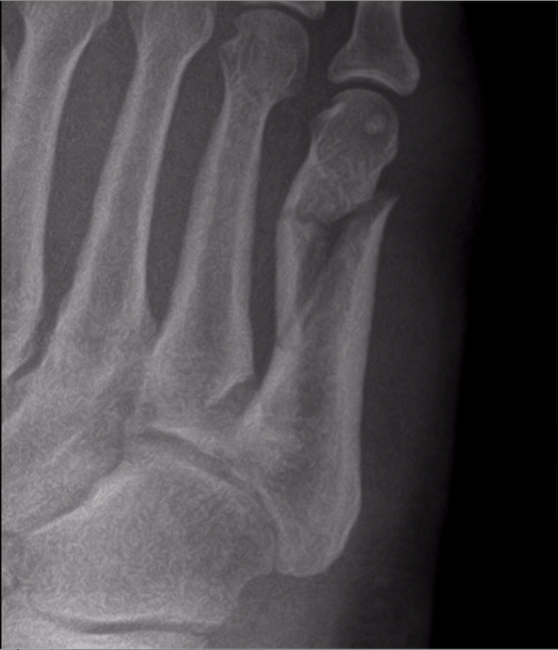

A 58-year-old female with past medical history of gastroesophageal reflux disease (GERD), hypothyroidism, and bronchitis presented to the podiatry clinic with chief complaint of pain to the lateral aspect of the right foot after suffering a fall. She was a former smoker with a one-pack-per-day, 18-pack-year history, having quit 20 years ago. On exam, the patient had palpable 2/4 pedal pulses and no neurological deficits. Ecchymosis and swelling were noted to the lateral aspect of the foot. X-rays were obtained, demonstrating a closed, displaced fracture of the fifth metatarsal shaft with a butterfly fragment and shortening (Figure 1).